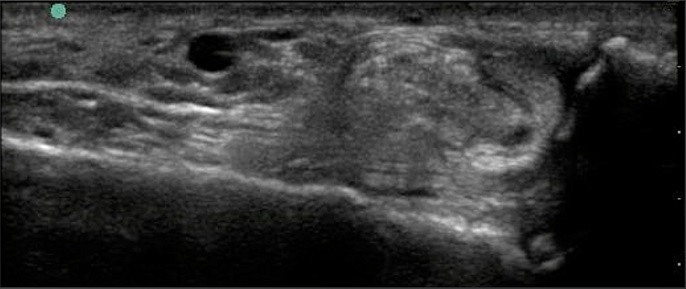

Foot & Ankle Peroneus Brevis Split Tear 1 Image